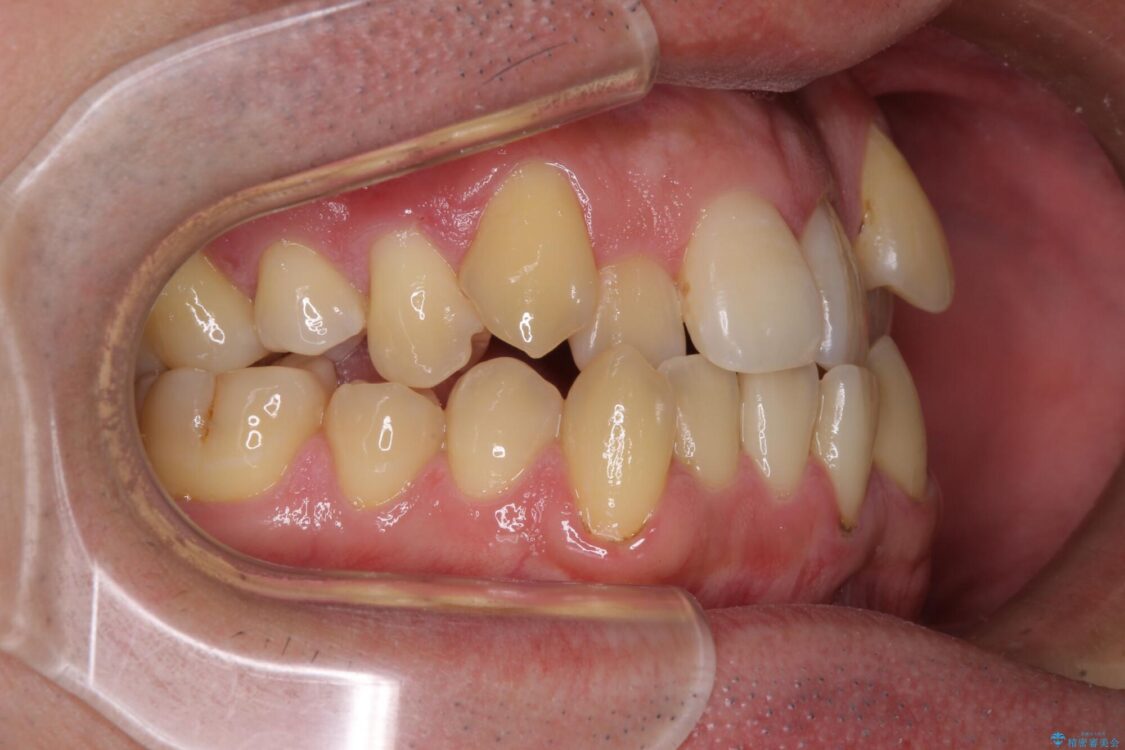

八重歯と前歯のクロスバイトを改善したいとのことで来院された患者様です。

デコボコの程度は強かったのですが、口元の突出感はなかったため、非抜歯矯正としました。

治療前

• 八重歯とクロスバイト 目立たないワイヤー装置で矯正治療 治療前画像